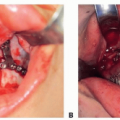

Determine what type of implant material and size of custom skull implant that are needed to rebuild the skull thickness and shape (HTR-PMI, Titanium, PEEK, PEKK material options).1

Choice of implant is based on surgeon preference. There is no proven biologic advantage to any implant material over any other. However, they do have different handling characteristics.1,2